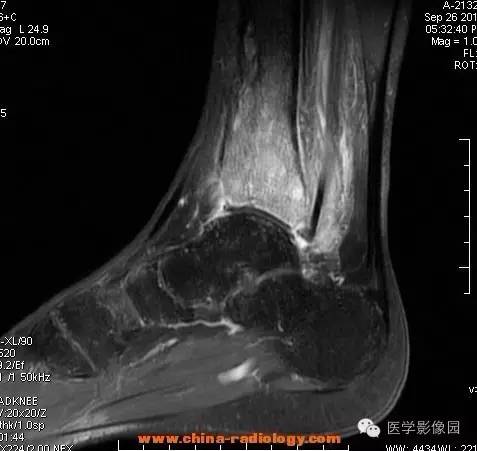

【病例】胫骨骨脓肿1例MR影像表现

影像学表现:胫骨中下段干骺端不未规则形长T1长T2信号,T2WI见不完整环形稍低信号影,T2脂肪抑制低信号更明显,并见胫骨下段及踝关节后外侧软组织呈弥漫稍高信号,增强明显不均匀强化,增强见低信号环内有环形强化影。

影像学表现:表现为长骨干骺端有椭圆形密度减低区,边缘有清晰的骨质硬化,病变与邻近正常骨髓腔境界清楚。MRI上T1WI呈低信号,少数呈等信号,T2WI多为混杂高信号,增强扫描可见环状强化,强化的脓肿壁薄而均匀。